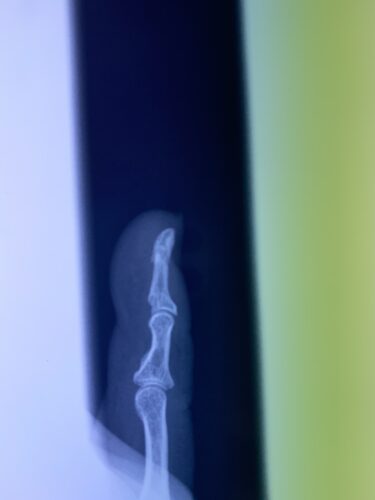

第16回整骨研究会「賜恩」研修会開催

さわやか千葉県民プラザ(指骨骨折)

第18回整骨研究会「賜恩」研修会開催